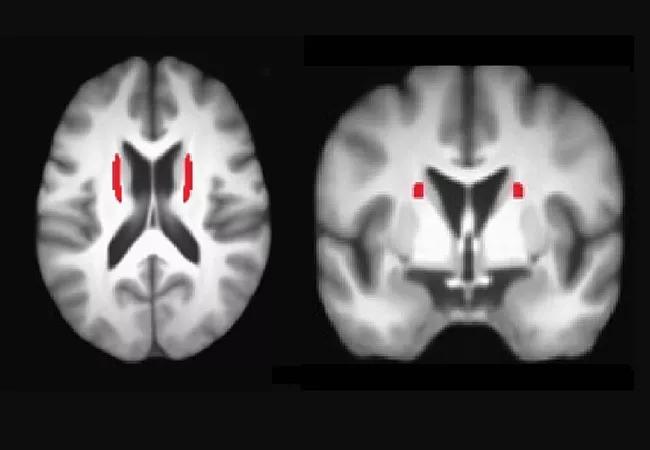

In our most recent study,3 we used diffusion tensor imaging (DTI) to examine longitudinal changes in structural connectivity in prHD. DTI measures the integrity of white matter fiber tracts in the brain. We found that longitudinal changes in diffusivity, measured on an annual basis for two years, were localized to a white matter fiber tract called the superior fronto-occipital fasciculus (Figure). These changes were most prominent in individuals closer to a manifest diagnosis. Increases in motor symptoms across time were associated with greater changes in the superior fronto-occipital fasciculus diffusivity over time, in addition to atrophy of basal ganglia (putamen and caudate). These findings provided novel insights into longitudinal changes in different facets of structural brain connectivity in prHD.